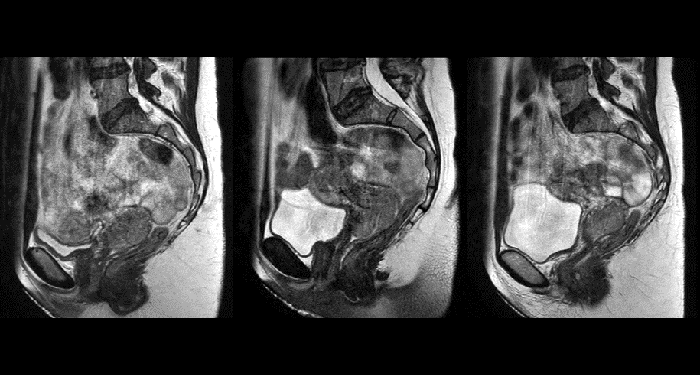

With its exceptional soft-tissue visualization capabilities and wide range of image contrasts, MRI has become a powerful tool to help more precisely define tumor boundaries. This is particularly important as it has been established that there is a high degree of uncertainty in target volume delineation, and it is even reported to represent the largest uncertainty in the entire radiotherapy process for most tumor sites**. Better visualization of the target area and nearby organs-at-risk is a key factor in enhancing target volume delineation. MRI’s expanding role also can be attributed to its functional imaging capabilities, which can inform both target characterization and treatment response.

With its superior soft tissue contrast compared to CT, MRI offers exquisite visualization of tumor boundaries and proximity to nearby critical structures.